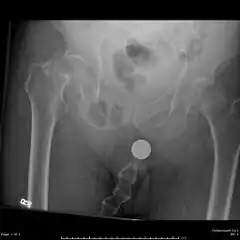

| X-ray image of a femoral shaft fracture | |

A femoral fracture is a bone fracture that involves the femur.[1] They are typically sustained in high-impact trauma, such as car crashes, due to the large amount of force needed to break the bone. Fractures of the diaphysis, or middle of the femur, are managed differently from those at the head, neck, and trochanter

Radiography

Anterior-posterior (AP) and lateral radiographs are typically obtained.[4]

In order to rule out other injuries, hip, pelvis, and knee radiographs are also obtained.[5]

The hip radiograph is of particular importance, because femoral neck fractures can lead to osteonecrosis of the femoral head.[4]